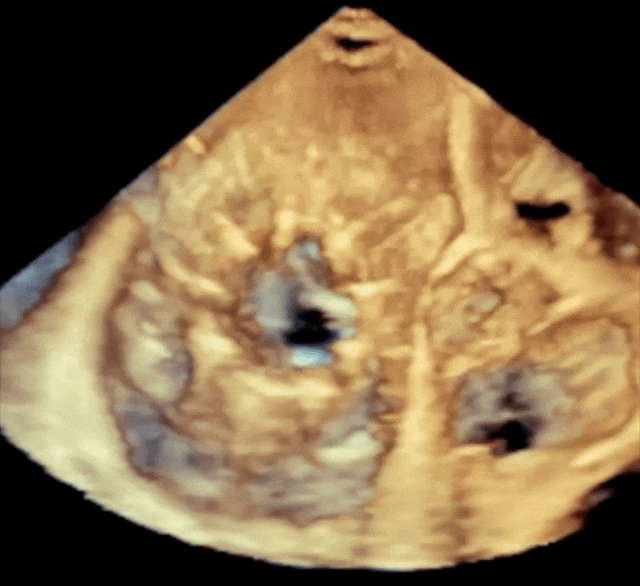

Echokardiografia to nie tylko narzędzie diagnostyczne, ale również jedyna technika wizualizacyjna pozwalająca na przestrzenną nawigację podczas przezcewnikowych zabiegów wewnątrzsercowych w czasie rzeczywistym. Od początku wprowadzenia echokardiografii trójwymiarowej czasu rzeczywistego (TTE Live3D 2001 i TEE Live3D 2007) praktycznie codziennie korzystam z tych technologii w diagnostyce i terapii...

Przezklatkowa i przezprzełykowa

Echokardiografia